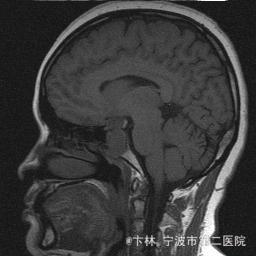

予以完善血,尿,粪常规检查,及凝血功能全套,输血功能全套及垂体功能全套,蝶鞍冠状CT等术前检查措施,行经蝶入路垂体瘤切除术。术后予以对症,补液,调节血电解质等治疗,患者视力明显改善,复查头颅MRI提示肿瘤基本全切,一周后患者出院。

此病人颅内垂体瘤体积较大,突破鞍隔压迫视交叉,故患者视力视野障碍为首发症状,该肿瘤主体有大部分向蝶窦腔生长,因此采用经蝶手术入路,肿瘤切除满意,术后患者视力视野恢复满意,。